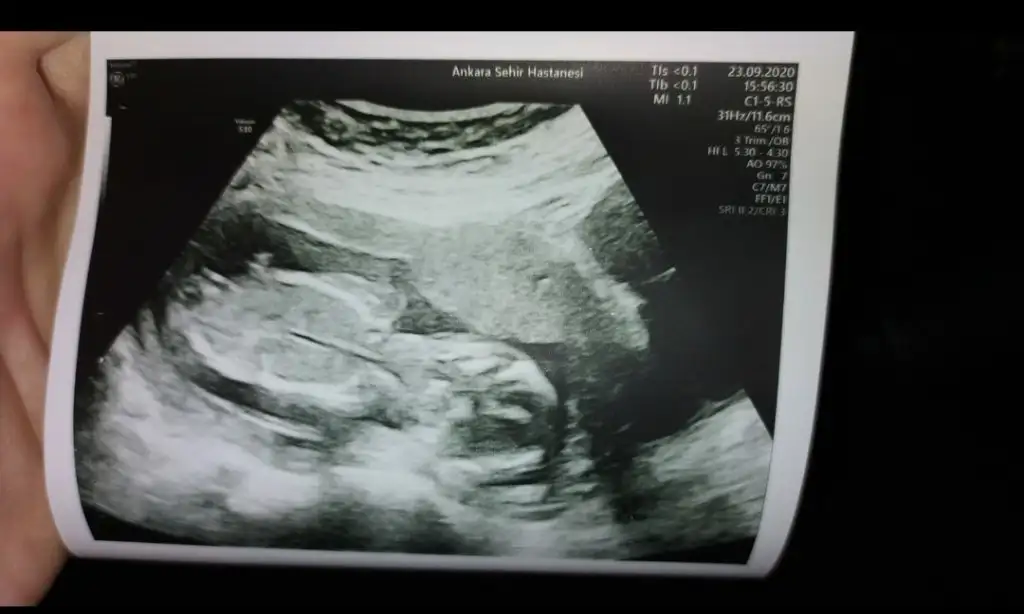

Bnada yorum yapar Mısın

Bnada yorum yapar Muş’un cnmErkek büyük ihtimal canım